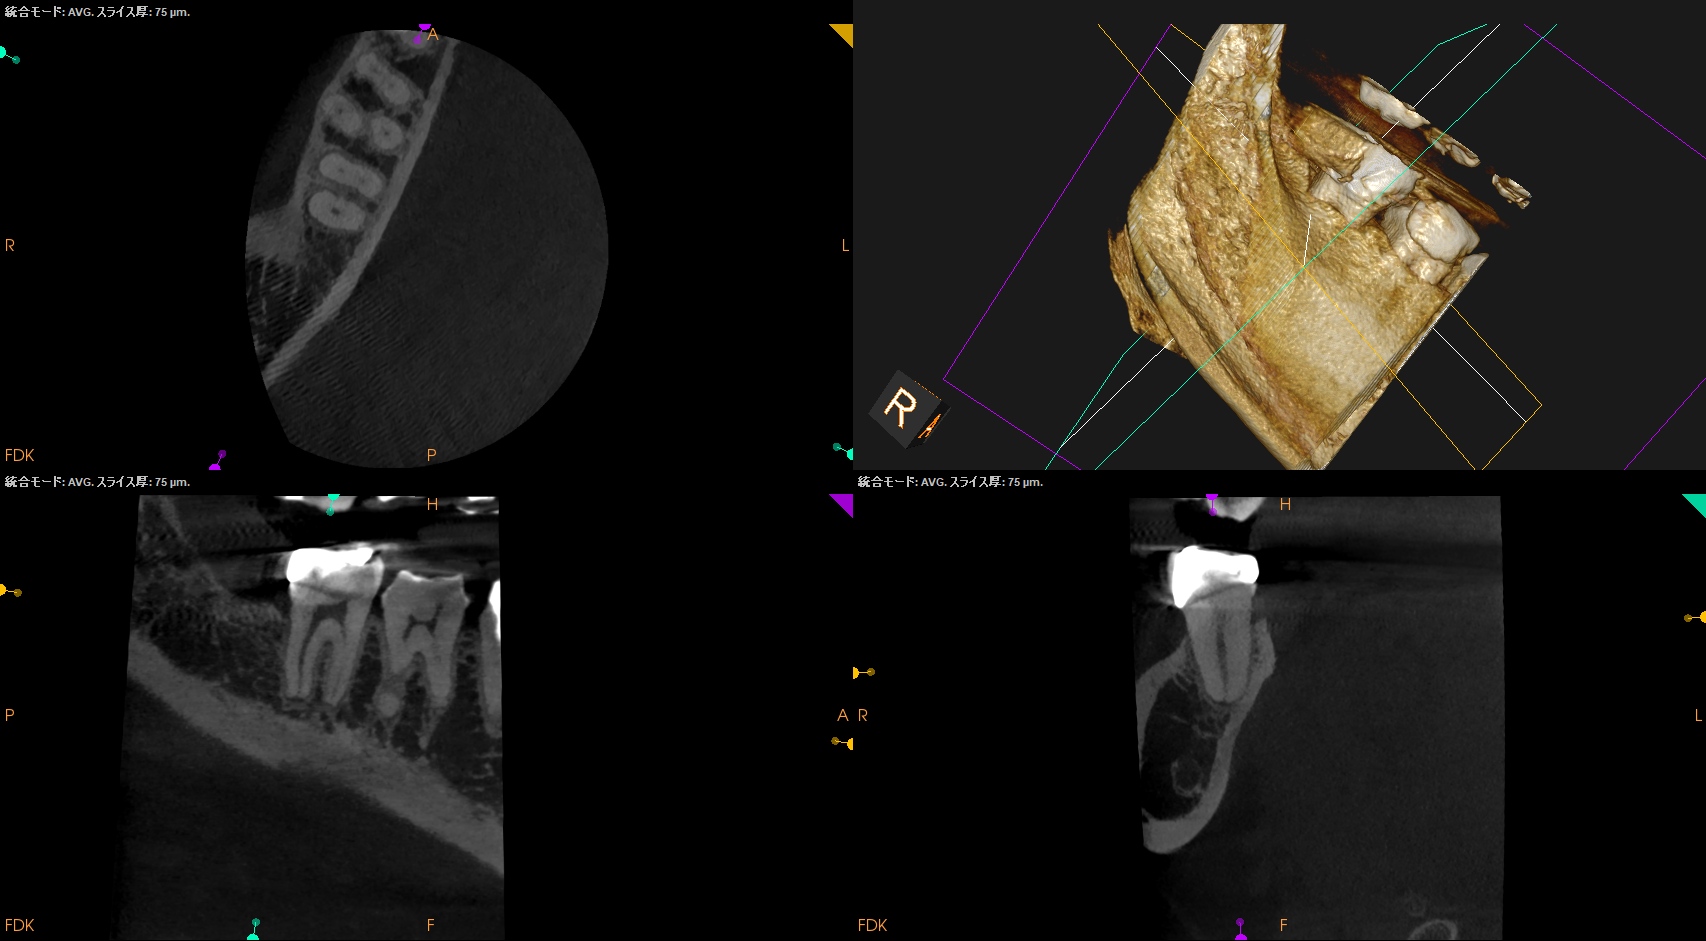

以下のように根管形成した。

Dは#60.02で形成しても出血がペーパーポイントに見られたためにProTaper Gold F5まで形成した。

ML,MBは合流していることが多いと言う解剖学的情報をもとに以下のように合流部分をチェックした。

問題はないだろう。